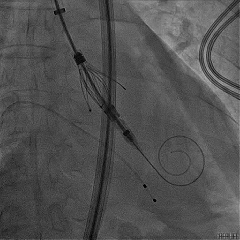

TAVR手术过程

主动脉瓣大量反流

回撤导引鞘,定位键顺利展开

输送器调弯

定位键解离

推送入窦形态改变不明显

无窦瓣叶脱垂影响瓣叶夹持

回撤后增加调弯夹持瓣叶

右窦中心造影确认瓣叶夹持

食道超声确认瓣叶夹持

经胸超声确认右冠瓣叶夹持

回撤MP导管,一键释放瓣膜

松弯后输送器回撤至大鞘,更换小鞘

术后右窦中心造影,无漏,无AVB